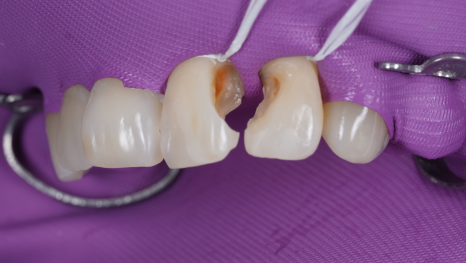

촬영일 : 251230

불완전한 경계 부분으로 충치도 새로 생겨 큐레이로 계속 확인하면서 충치를 제거해 줬습니다.

그 후 레진 빌드업 단계에 들어갔는데요.

한 번에 두껍게 메우는 것이 아니라

아주 얇은 층을 여러 번 쌓아 올려야

자연스러운 빛 반사와 단단한 내구성을

얻을 수 있어요.